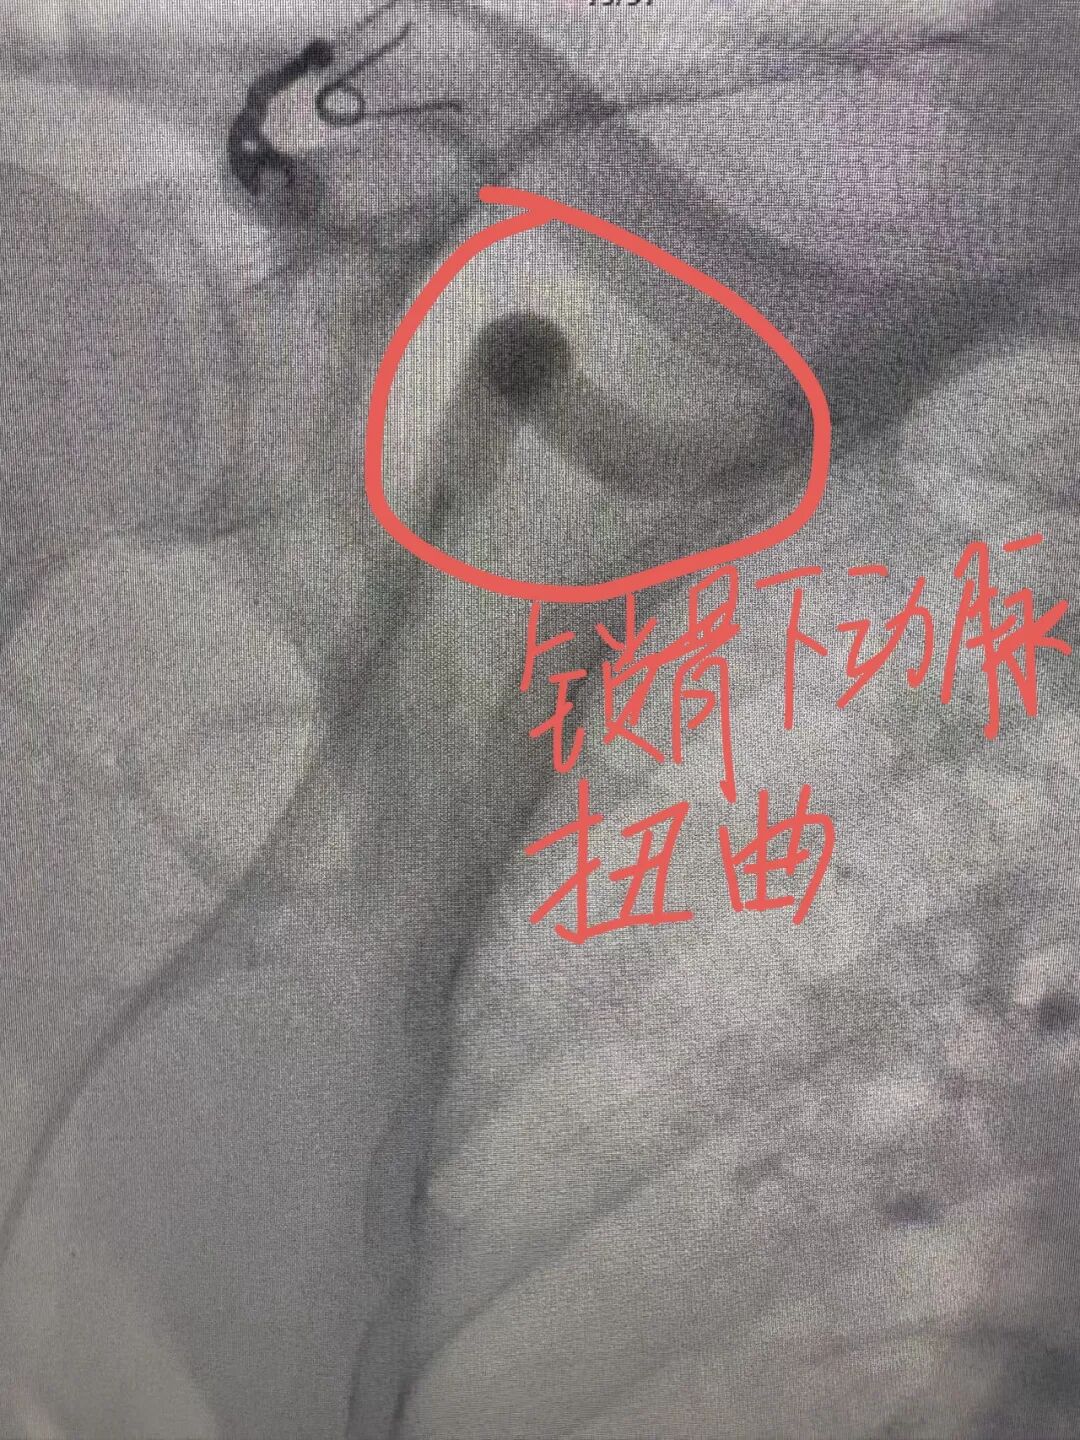

介入术中发现,在常规右侧桡动脉入路时,发现患者的桡动脉、肱动脉、锁骨下动脉血管严重扭曲,仿佛是一条蜿蜒曲折、布满荆棘的山路,导丝难以通过,手术一度受阻。关键时刻,介入团队冷静应对,主治医师罗科伟凭借娴熟技术与对血管结构的精确把握,耐心调整导丝方向,最终顺利将其送至主动脉根部,成功完成造影。